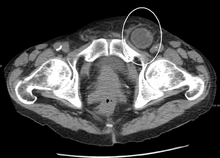

After the diagnosis is suspected, it is often confirmed by imaging. When assessed by ultrasound or cross sectional imaging with CT or MRI, the major differential in diagnosing indirect inguinal hernias is differentiation from spermatic cord lipomas, as both can contain only fat and extend along the inguinal canal into the scrotum.[9]

On axial CT, lipomas originate posterolateral to the cord, and are located inside the cremaster muscle, while inguinal hernias lie anteromedial to the cord and are not intramuscular. Large lipomas may appear nearly indistinguishable as the fat engulfs anatomic boundaries, but they do not change position with coughing or straining.[9]